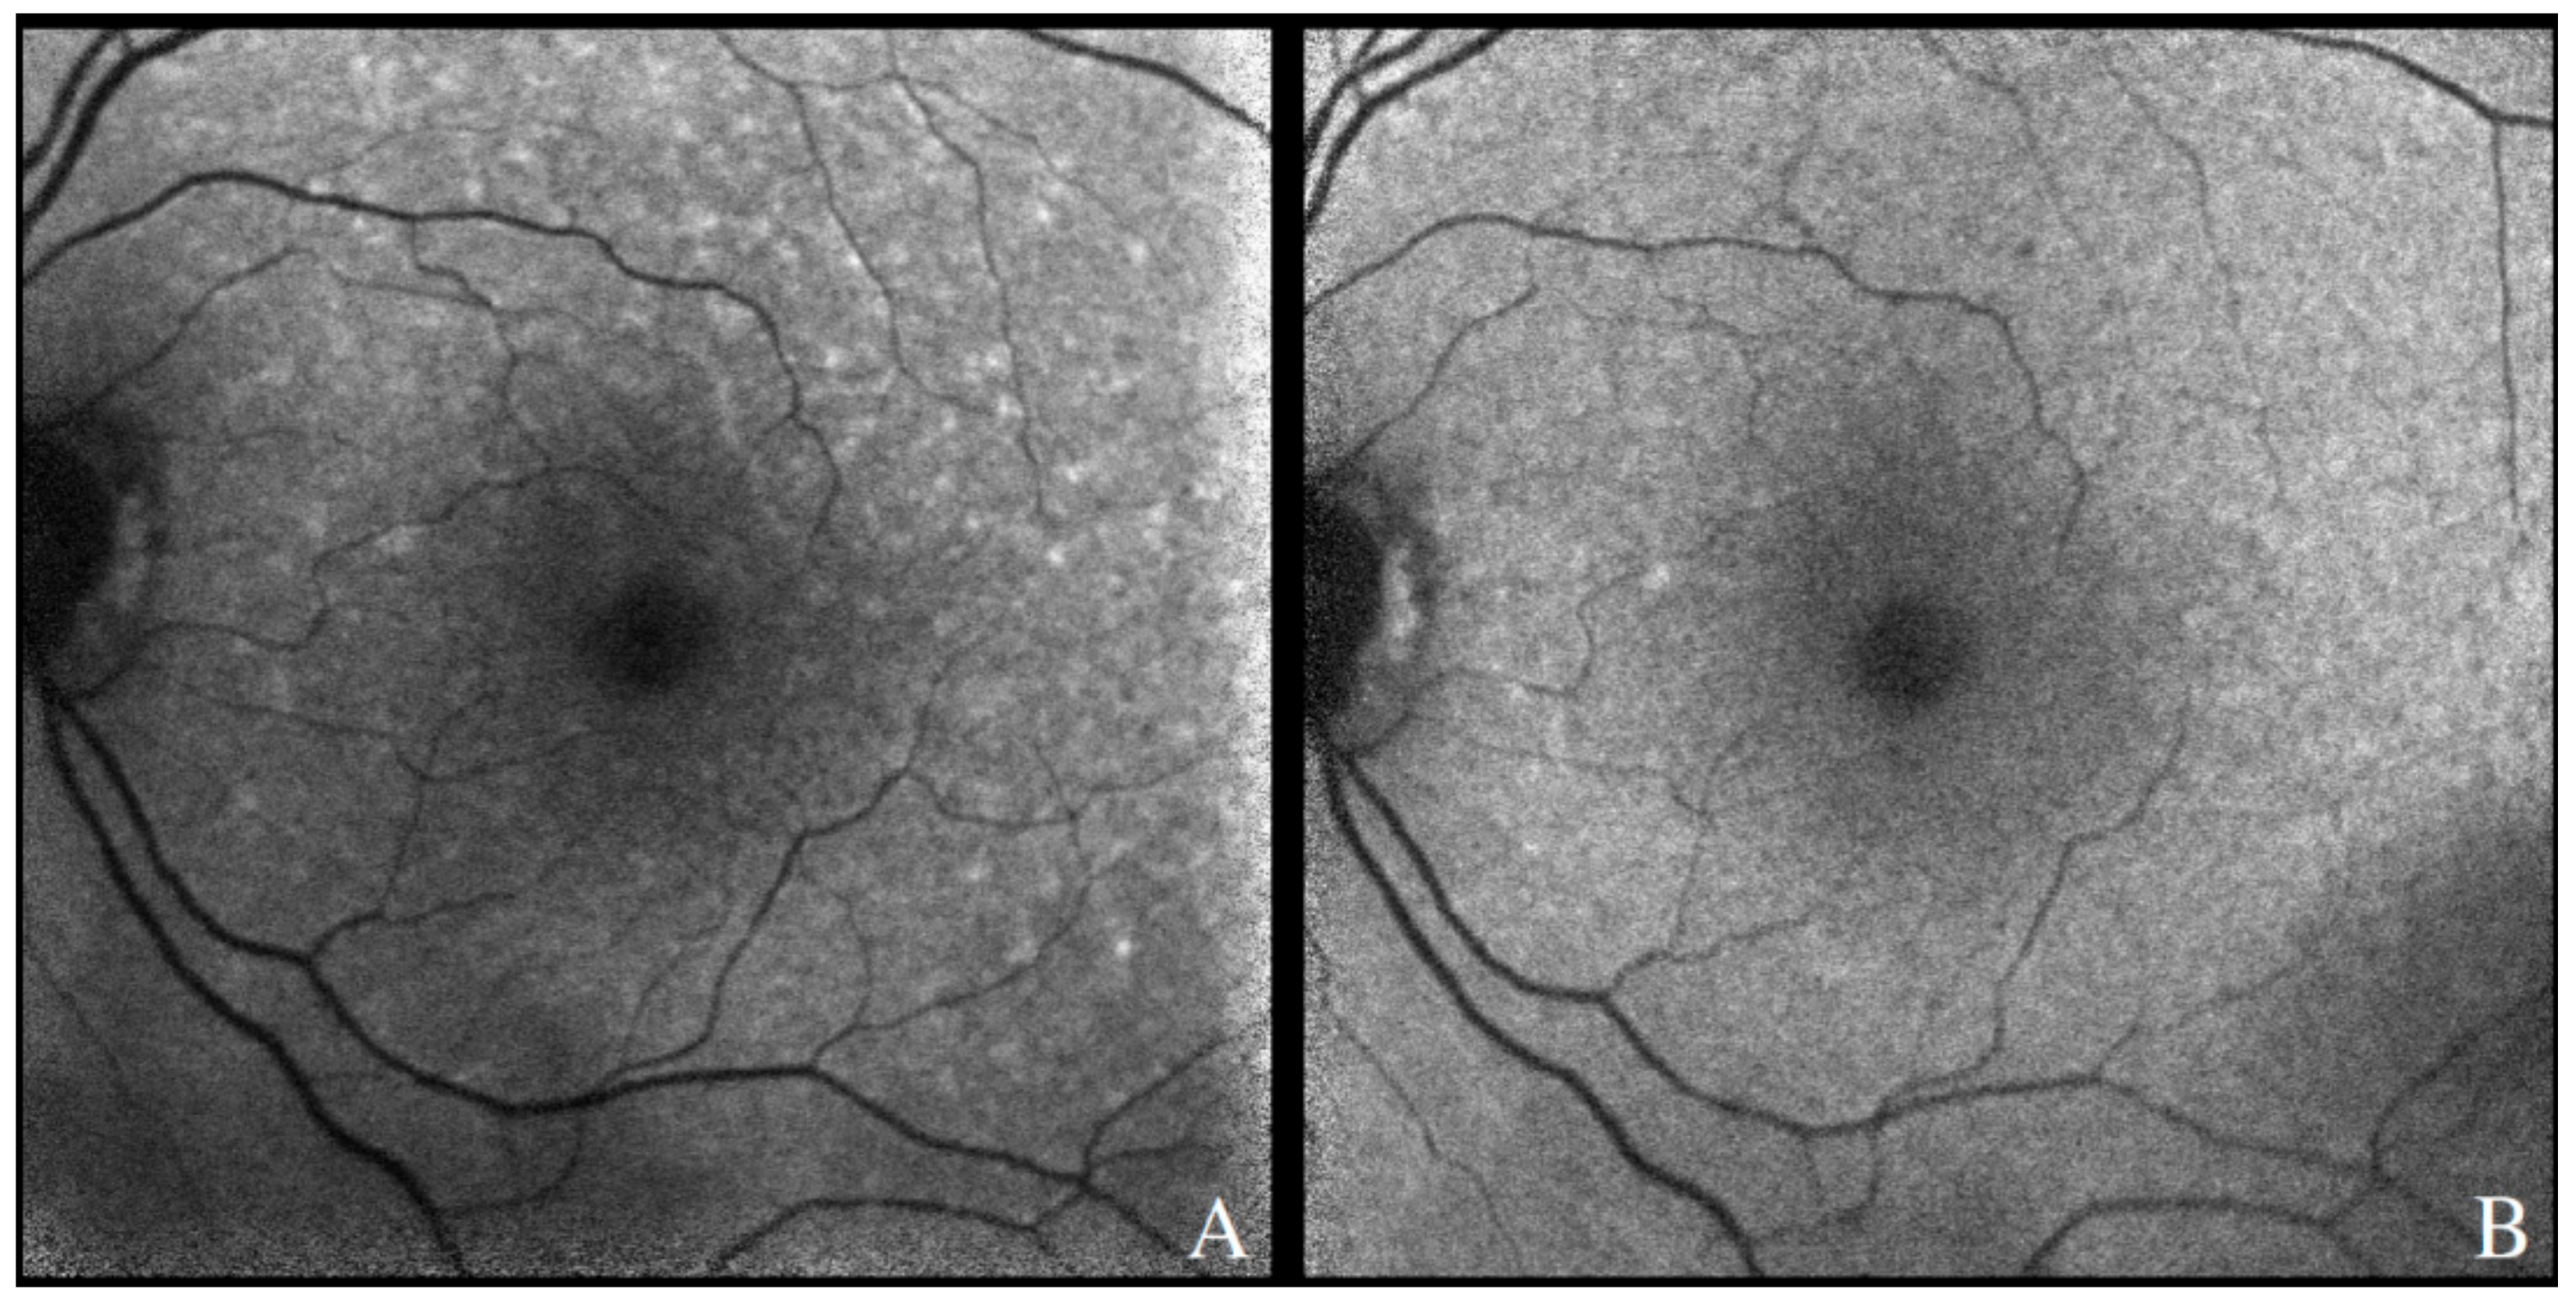

4.1.1. Fundus Autofluorescence

4.1.2. Spectral Domain Optical Coherence Tomography